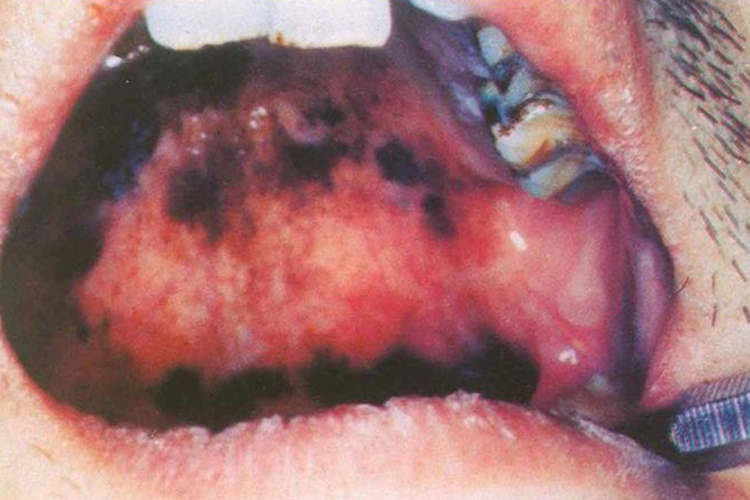

口腔上颚发黑可表现为局部突出的血疱,或不突出的黑棕色斑片。

创伤性血疱导致的口腔上颚发黑,病损处可达20-30mm,易发生于咀嚼一侧和软硬颚交界处,初起疱液鲜红,旋即变为紫黑色,可在上颚部位形成一发黑的水疱,疱壁薄容易破裂,淤血流尽后留有鲜红色疱底创面,疼痛明显,可影响吞咽。